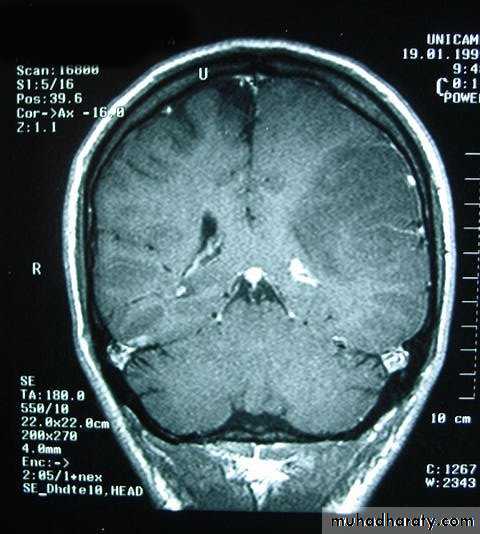

Metastatic Brain Tumours

Metastatic Brain Tumours Pre contrast CT

Metastatic Brain Tumours Post contrast CT